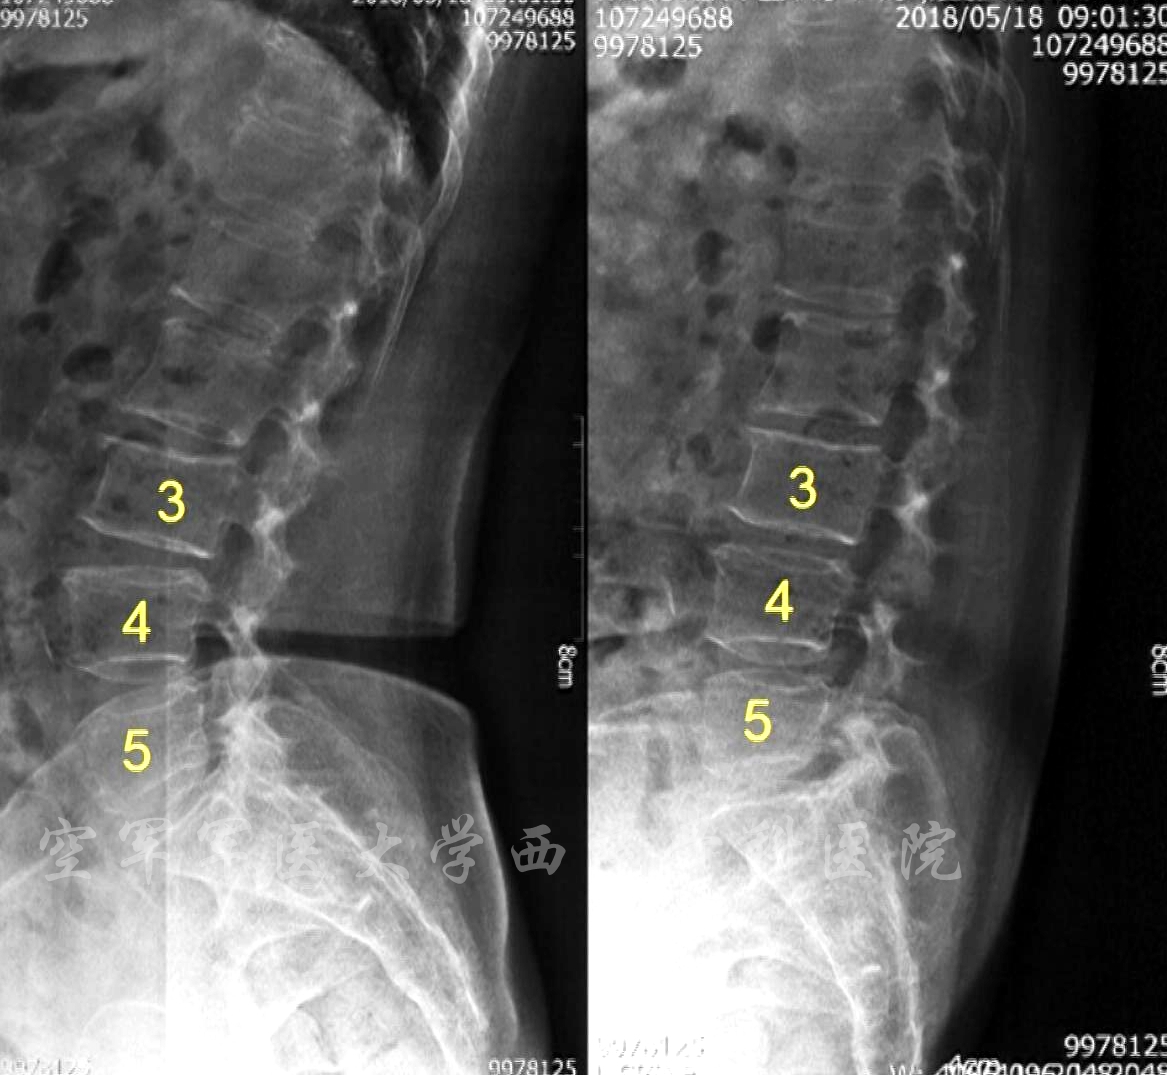

术前X线动力位片

术前MRI